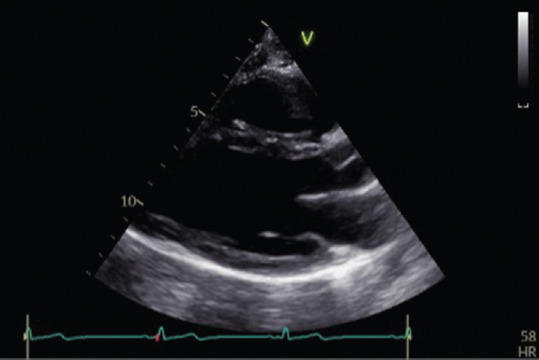

Abstract Image